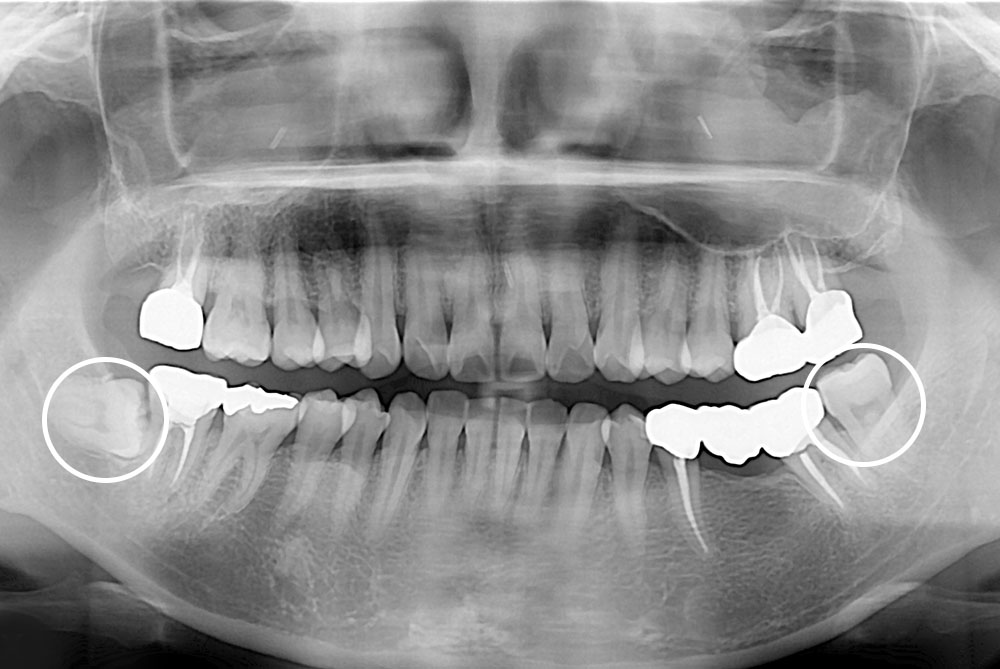

[사랑니] 매복 사랑니 발치

치료후 : 2019-12-02

세종치과는 구강악안면외과학 박사이신 원장님이 발치하는 치과입니다.